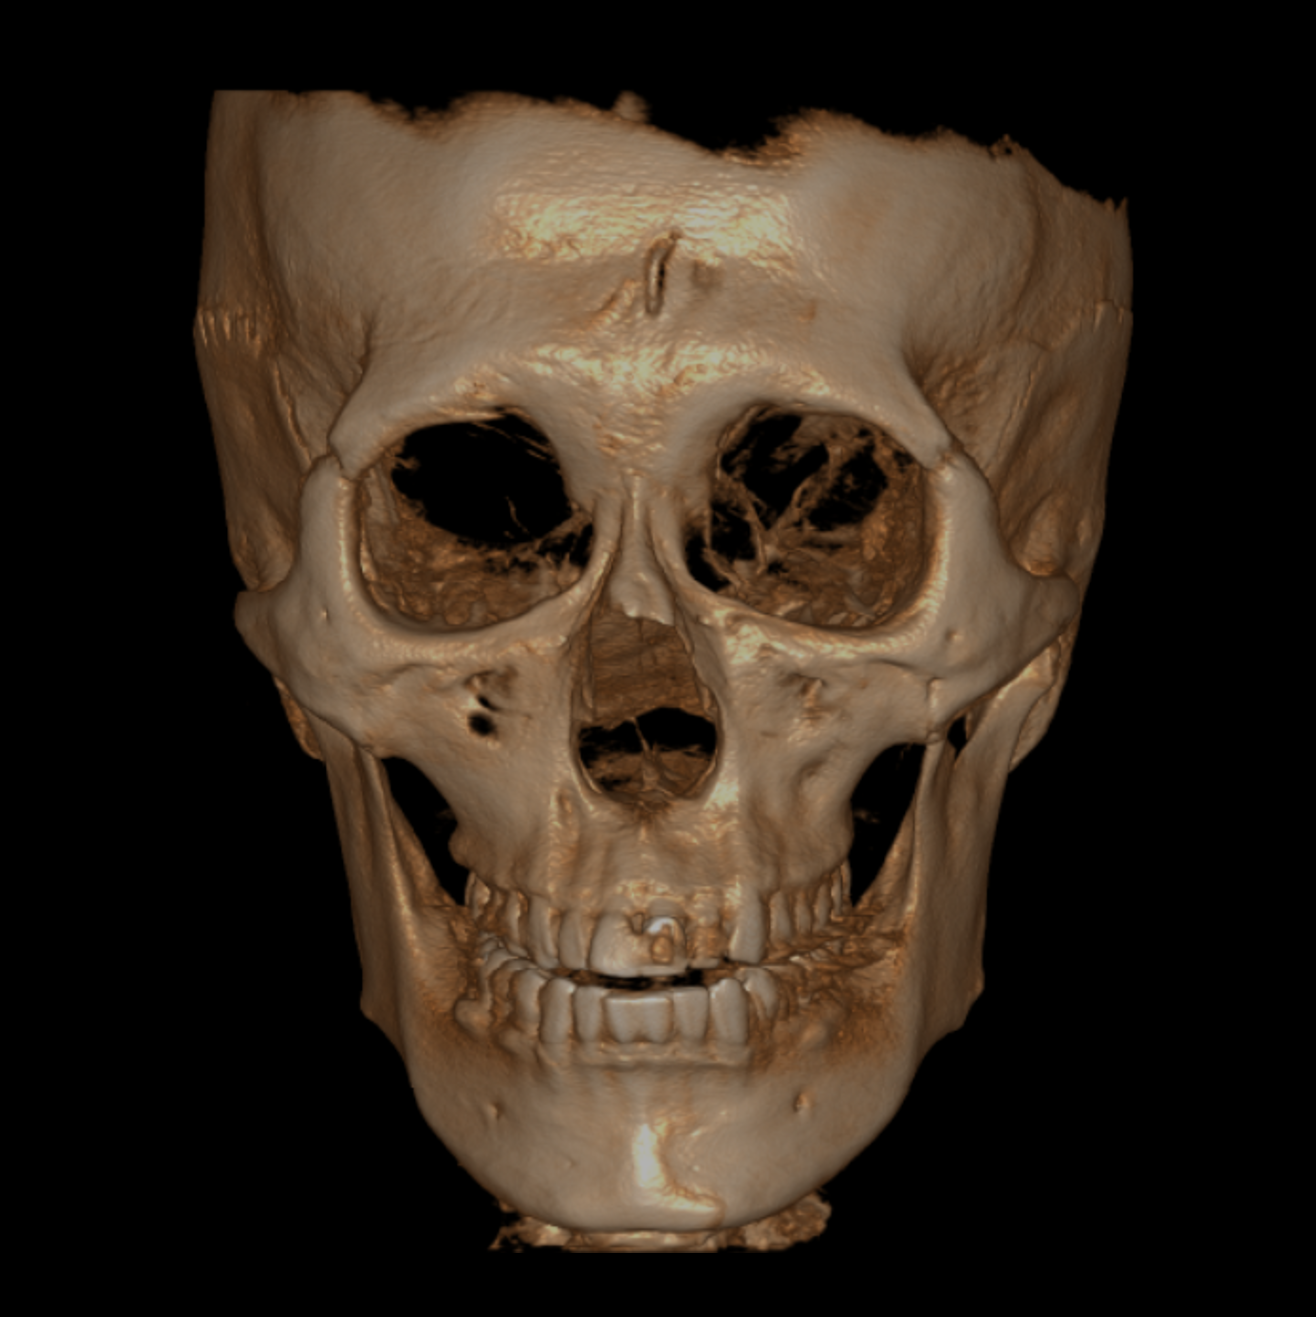

Large & Free FOV(Field of View)

With a freely adjustable FOV and a maximum coverage of up to 20x20 cm(4T), 17.5x15(2T) bright CT supports a wide range of clinical applications—from tooth-focused localized diagnosis to facial skeletal analysis. Clinicians can customize the optimal scanning area for the specific treatment needs, enhancing diagnostic efficiency.